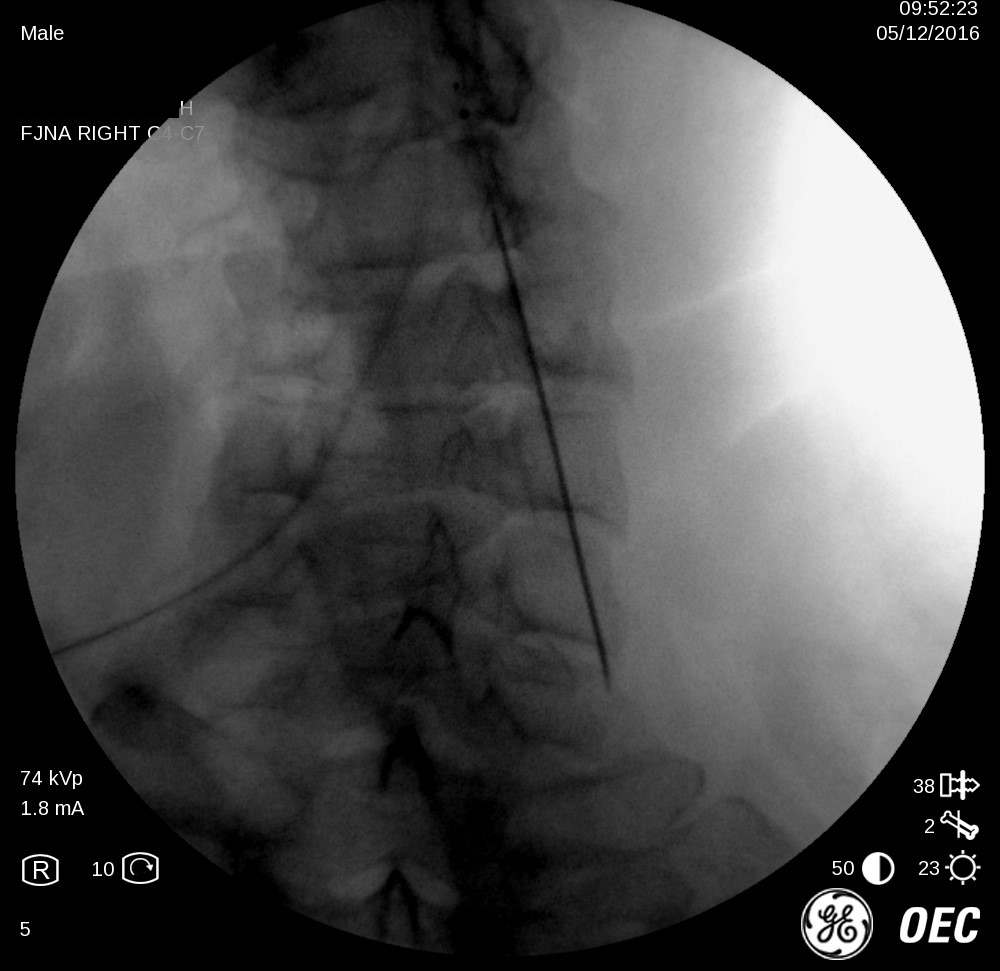

1-Facet-Denervation-Anatomage-Dr.-Hany-Wahib-Anatomy-Dept.-Ain-Shams-Univ.-1